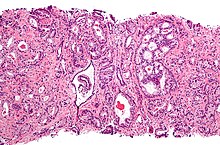

Micrograph showing a prostate cancer (conventional adenocarcinoma) with perineural invasion. H&E stain.

A histopathologic diagnosis mainly includes assessment of whether a cancer exists, as well as any subdiagnosis, if possible. Histopathologic subdiagnosis has implications for the possibility and methodology of Gleason scoring.[85] The most common histopathological subdiagnosis is acinar adenocarcinoma, constituting 93% of diagnoses.[86] The most common form of acinar adenocarcinoma, in turn, is "adenocarcinoma, not otherwise specified", also termed conventional, or usual acinar adenocarcinoma.[87]

Micrograph of prostate adenocarcinoma, acinar type, the most common type of prostate cancer. Needle biopsy, H&E stain